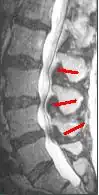

MRI

Since an MRI provides excellent imaging of blood vessels and tissues, it is recognized as the best type of imaging to observe signs associated with lumbar compression. The precise measurement of the diameter of the spinal canal is a particularly important component when determining the severity of the stenosis itself.[2] High strength 3-Tesla MRI machines are being utilized due to the increased vascular imaging capabilities. Better resolution capacity allows for more detailed observations by the healthcare provider. The sharp contrast of the high power MRI outlines details in the vertebra that are critical when examining a patient with lumbar spinal stenosis who may need a laminotomy.[1] MRI scanning post invasive surgery is used to see the quality of the surgery itself, yet the appropriate postoperative time elapsed before conducting an MRI is a debated topic.[2]